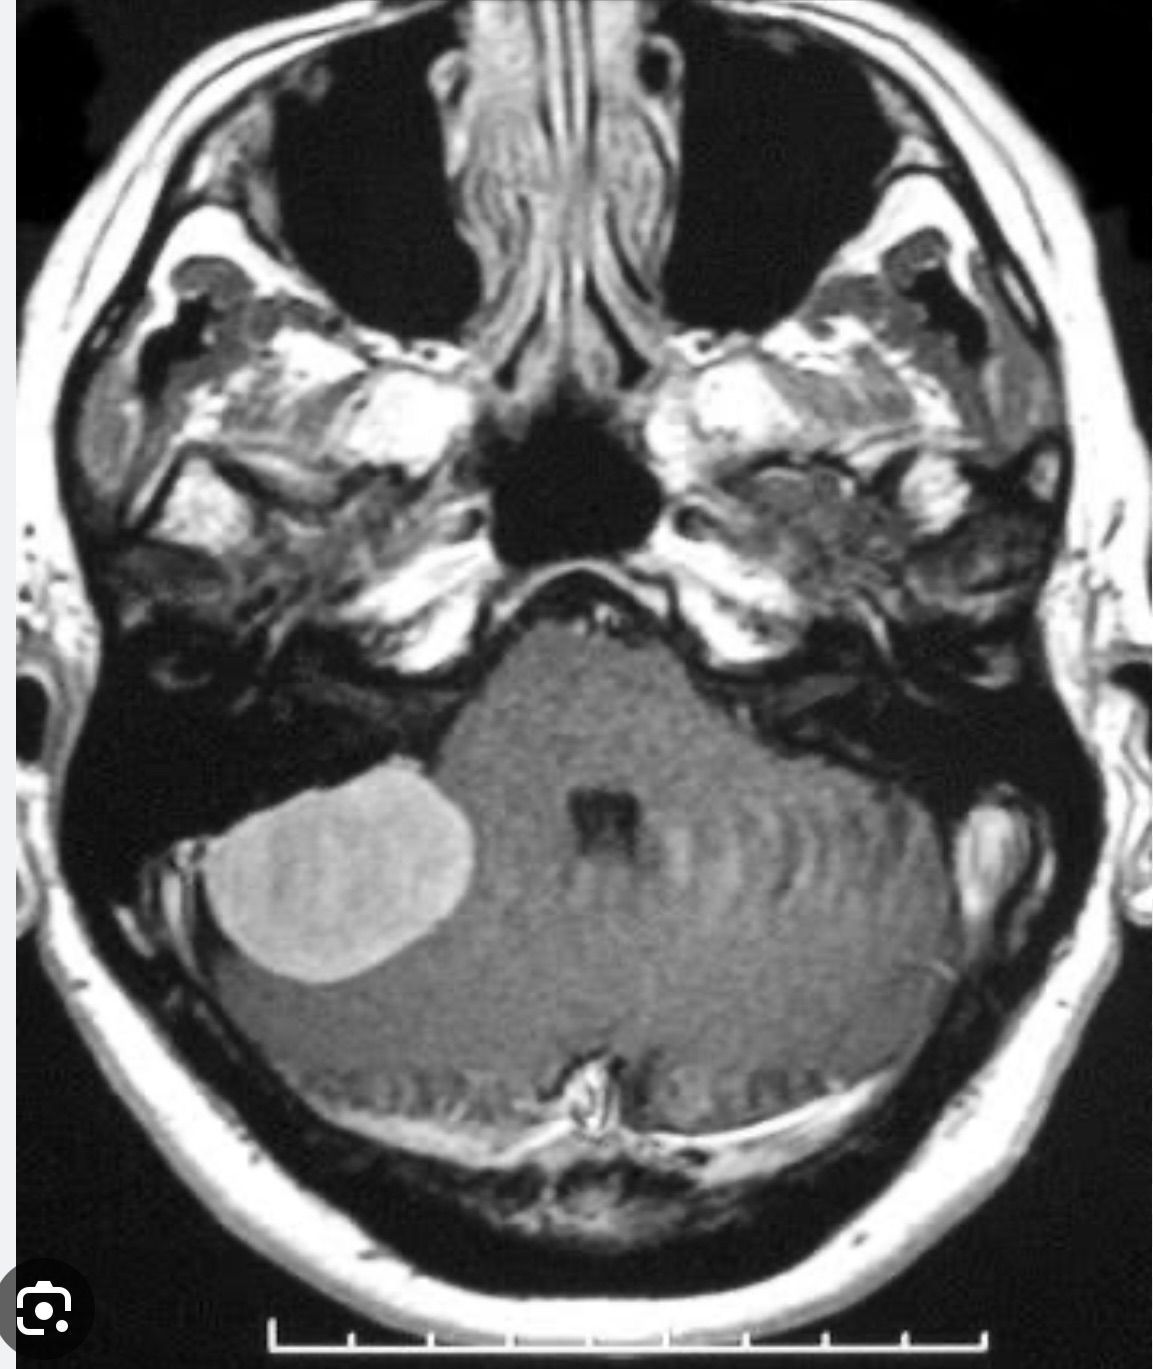

Cerebellopontine angle tumors (CPAs) occur between the lower part of the brain and the brain stem. Most CPAs are benign, but can cause nerve damage or compress the brain stem if not treated. About 90 percent of the time, the first symptom is hearing loss in one ear, accompanied by tinnitus, ringing in the ears. Others symptoms include speech impediment, disequilibrium, tremors, and loss of muscle control.